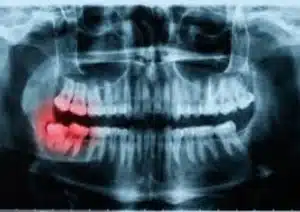

If we have reason to assume that your dental problem is located deeper in your tooth, the periapical x-ray will reveal the whole anatomy of the tooth, including the pulp and nerve canals, as well as the surrounding roots and bone. In this instance, the periapical x-ray will be taken.

If we are dealing with a tooth with an abscess, this film will display a black shadow at the end of the root. In addition to aiding in the diagnosis of your condition, a periapical examination will provide the information necessary to identify the most efficient approach of treatment. For example, if there is adequate healthy tooth structure remaining and the nerve anatomy within your tooth is typical, we will likely recommend root canal therapy to fix it. This will enable us to eliminate the infection and preserve your tooth. If the x-rays taken at the dentist’s office reveal that too much of the tooth is gone, the tooth will need to be pulled.

When we inspect the tooth’s roots, it will be easier for us to determine whether or not you need to see an oral surgeon to have a tooth out. If the roots are very large and curved, or if there are significant nerves flowing through the area, you may be referred to a specialist for your own protection.